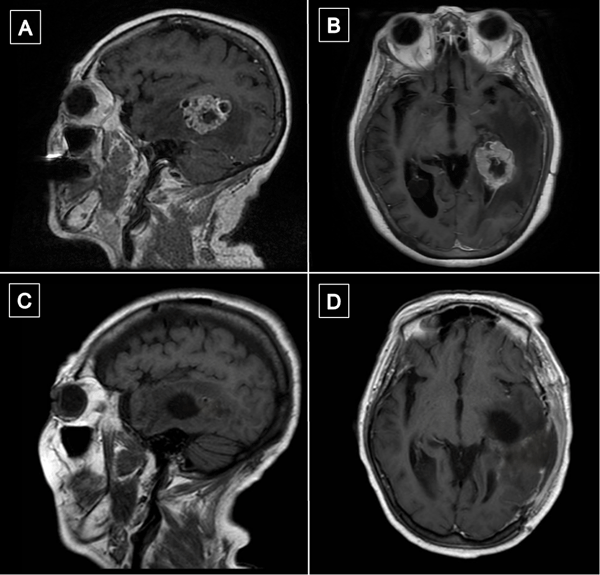

La resonancia magnética (RM) de encéfalo con gadolinio evidenció una lesión expansiva heterogénea, con áreas centrales de aspecto quístico y degeneración necrótica, localizada en la topografía temporomesial izquierda de aproximadamente 28 × 27 mm en plano axial y 29 × 26 mm en plano coronal, con realce heterogéneo tras la administración de contraste endovenoso. En secuencia de susceptibilidad magnética presentaba signos de restos de hemosiderina y/o microcalcificaciones. En el asta occipital y el atrio ipsilateral del ventrículo lateral, se evidenciaron formaciones quísticas con refuerzo periférico. La lesión descripta presentaba edema perilesional que comprometía el lóbulo temporal izquierdo y la región parietoccipital ipsilateral. Además, se observó dilatación del tercer ventrículo y ventrículo lateral homolateral. Las cisternas perimesencefálicas se encontraban libres, y las estructuras de la línea media, centradas. Las imágenes obtenidas eran sugestivas de una lesión de origen glial de alto grado (Figura 1). Se complementó con tractografía en la que se observó una disminución de la fracción de anisotropía a nivel del septum sagital con disrupción de las fibras de los tractos arcuato, frontooccipital inferior y longitudinal inferior izquierdo (Figura 2).

Figura 1. RM preoperatoria con contraste endovenoso. A y B) RM de encéfalo, cortes axial y sagital, respectivamente, en secuencia T1 contrastada, que evidencia lesión expansiva con realce heterogéneo localizada en topografía temporomesial izquierda. C) Corte axial en secuencia T2, se muestra heterogeneidad de la lesión con áreas centrales de aspecto quístico y degeneración necrótica. D) Corte axial en secuencia FLAIR que evidencia edema perilesional que compromete lóbulo temporal izquierdo y región parietooccipital ipsilateral.

Transcurrido un mes de la cirugía, se realizó resonancia magnética de encéfalo con gadolinio en la que se observó en la región temporomesial izquierda un área de señal líquida con signos de gliosis periférica y sutiles restos de hemosiderina, sin evidencia de lesión tumoral residual. Persistía el edema vasogénico con efecto de masa sobre el sistema ventricular ipsilateral (Figura 6).

Figura 6. Comparación de resonancias magnéticas pre y postquirúrgicas. A y B) RM prequirúrgica de encéfalo, cortes axial y sagital, respectivamente, en secuencia T1 contrastada, se evidencia lesión expansiva con realce heterogéneo localizada en topografía temporomesial izquierda. C y D) RM de encéfalo con gadolinio realizada aproximadamente un mes luego de la intervención quirúrgica. Cortes axial y sagital, respectivamente, en secuencia T1 contrastada en la que se evidencia en región temporomesial izquierda un área de señal líquida con signos de gliosis periférica, sin evidencia de lesión tumoral residual.